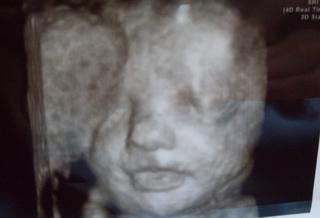

Baby práve sa chystám na 3D, držte päste aby sa konečne nezakrývalo krpaté nech viem čo to teda vlastne čakáme 🙄 😀

babyyyyy budeme mať kočku 😀 😀 😀 doktor spravil jeden záber a hovorí-tu je jeden pysk, druhý pysk a prestal hovoriť a čakal na našu reakciu.tak som nanho pozrela vyjavená jak debil a on že tak ste asi pochopili že budete mať dievčatko 😀 joooj to je taká sranda vedieť čo ma to tu stále kopce a šteklí 😀 a ani neviem ako ale rozhodli sme sa pre alexandru. teda manžel zatial hovori stale uvidime ale on to hovorit bude aj tesne pred krstom 😀 takže som sa s nou cely den rozprávala ako s malou sašou 😀 zajtra skusim dat nejake fotky...

elixia my sme platili 45€ za polhodinové vyšetrenie. všetko pozrel, premeral, skontroloval, spočítal (pršteky), dal niekolko fotiek, vytlačené vyšetrenie a jedno dvd a bol skutočne milý (i ked mam pocit že ked som ležala v nemocnici tak práve s nim som mala jednu nezrovnalosť 😝 ) my sme na tom s peniazmi dosť blbo ale tak ked už manžel objednal tak čo s ním... ale som rada že sme tam boli...

a teraz neviem či to ukáže ale snád hej-ešte som takto fotky nepridávala...hľa naša malá alexandra 🙂

Iji, tak to je bezva, holčička 🙂, fotečky krásné, my takové vůbec nemáme...